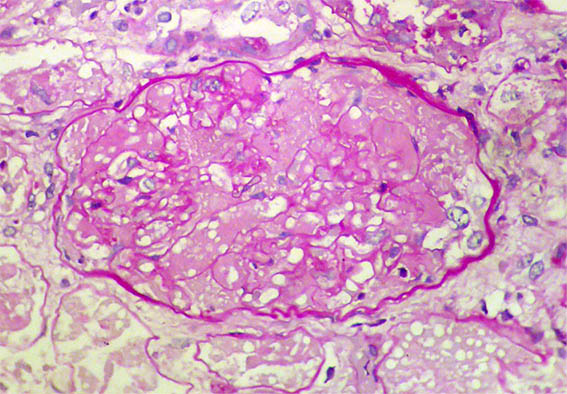

Figure 3. H&E, X400.Solidification, loss of many capillary lumens and erythrocyte fragmentation, without glomerulitis. .